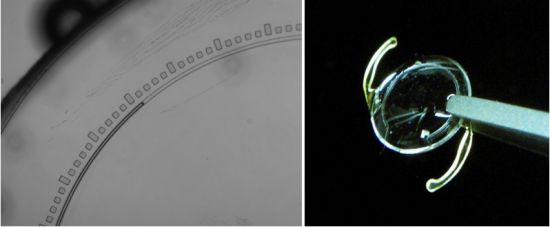

Çalışmaya göre önce göze bir mikroçip naklediliyor. Ardından hastalar, bir cep telefonu kamerası ve basit bir adaptör yardımıyla, 24 saat boyunca kendi kendine ölçüm yapabiliyor.

Yapılan cihazın mikroakışkan teknolojisi ile çalıştığını belirten Dr. Aracı, mikroçipin rutin katarakt ameliyatıyla hastaya nakledilebildiğini söyledi.

Aracı, “telefon ve optik adaptör ile gözün fotoğrafı çekilmekte ve yine cep telefonu ile bir analiz yapılıp, sonuçların doktora gönderilmesine imkan sağlamaktadır. Grubumuz, cihazları ameliyatla alınmış hayvan gözünde test etmiştir ve ileriki aşamada klinik testler gerekmektedir.” dedi.